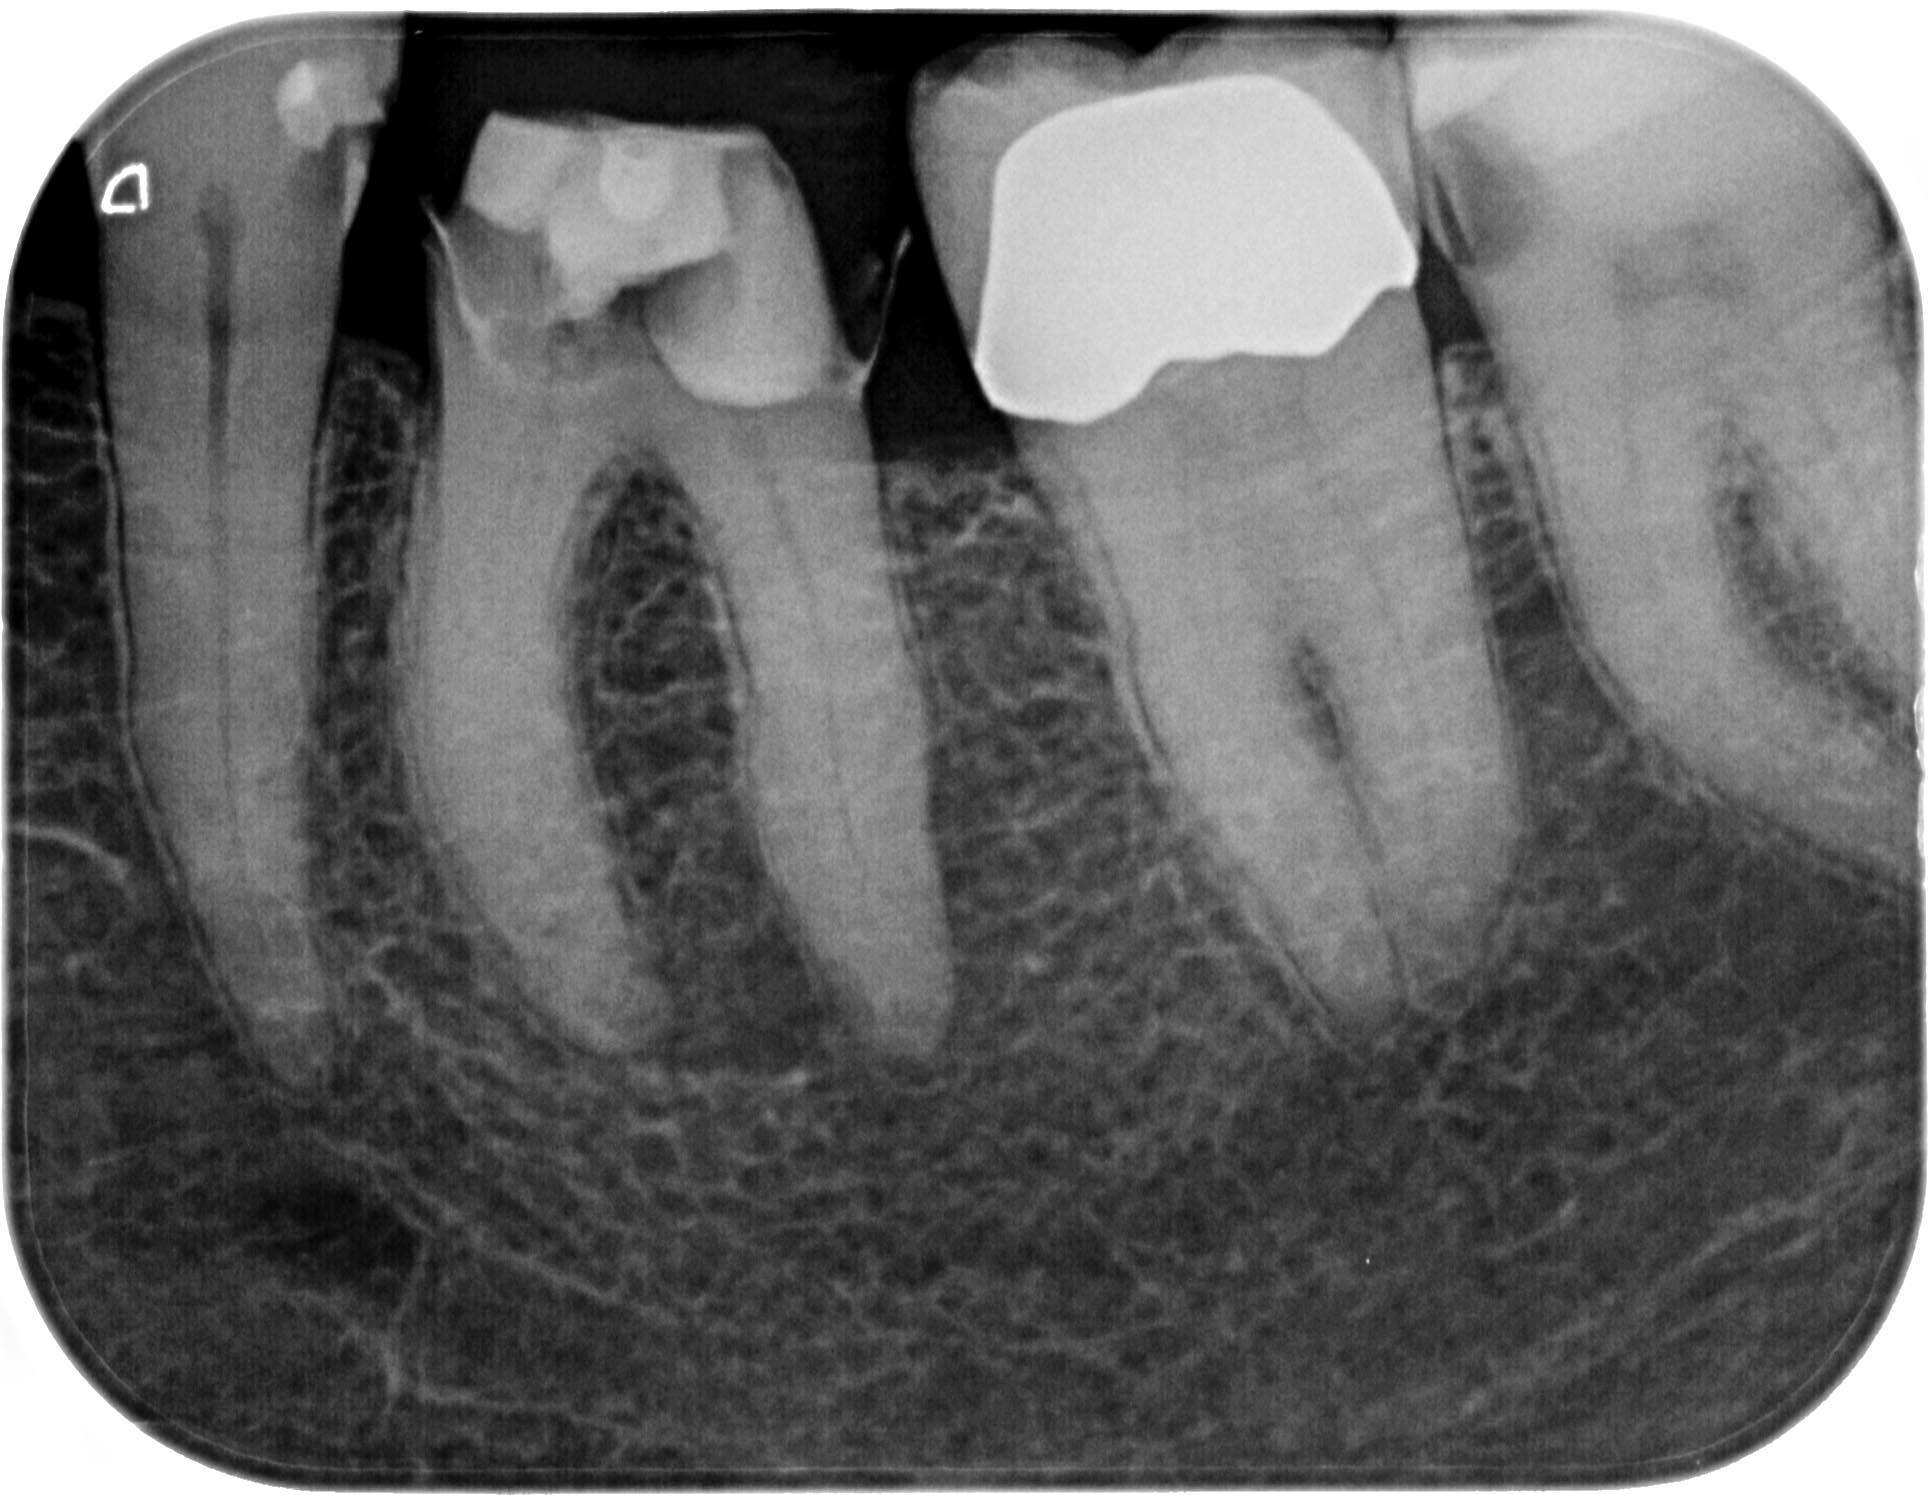

KSKrone6MonatepostWF-1-7 Veröffentlicht 24. September 2015 am 1929 × 1495 in Zuverlässige Endometrie bei Metallkronen – aber auch – Wäre das nicht eine sinnvolle neue Rubrik für WURZELSPITZE ? Zahn 36 vor Endo